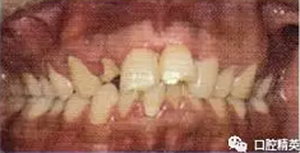

外傷后1周復(fù)查,電活力測試11:47,21:80,22:50,23:50,11RCT,根充恰填(圖3)。外傷后1個月拆除固定(圖4),電活力測試11:45,22:50,23:49。發(fā)現(xiàn)斗絲均為叩痛(±),松I°,2叩痛(一),不松。

圖4拆除固定后即刻口內(nèi)像